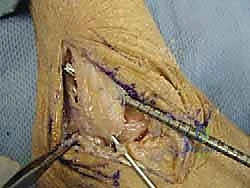

خطوات العملية الجراحية خطوة بخطوة مع الأستاذ الدكتور محمد هطيف

تتميز الجراحة في عيادة الدكتور هطيف بالدقة المتناهية واستخدام أحدث التقنيات العالمية. إليك كيف تتم العملية:

1. التخدير والتحضير:

تتم العملية عادة تحت التخدير النصفي أو العام. يتم تعقيم المنطقة وتجهيزها بدقة بالغة.

2. التقييم بالمنظار (Arthroscopy) بتقنية 4K:

قبل البدء في إعادة البناء، يقوم الدكتور هطيف بإدخال كاميرا دقيقة جداً (منظار) داخل مفصل الكاحل. تتيح شاشات الـ 4K رؤية تفاصيل المفصل بوضوح مذهل. يتم في هذه الخطوة تنظيف المفصل من أي أنسجة ملتهبة، إزالة الشظايا العظمية أو الغضروفية السائبة، ومعالجة أي تلف في الغضروف ناتج عن عدم الاستقرار المزمن.

3. تجهيز الطعم (Graft Preparation):

يتم تحضير الطعم الليفي (Allograft) وتشكيله بدقة ليتناسب تماماً مع الحجم والطول المطلوبين لتعويض أربطة ATFL و CFL المفقودة.

4. حفر الأنفاق العظمية:

باستخدام أدوات جراحية دقيقة، يقوم الدكتور هطيف بعمل أنفاق صغيرة جداً في عظم الشظية (Fibula) وعظم الكاحل (Talus) وعظم العقب (Calcaneus). تعتمد هذه الخطوة على المعرفة التشريحية العميقة لضمان وضع الأربطة الجديدة في مسارها التشريحي الطبيعي (Anatomical Reconstruction).

5. تثبيت الطعم:

يتم تمرير الطعم داخل الأنفاق العظمية وتثبيته بقوة باستخدام براغي تداخلية (Interference screws) مصنوعة من مواد تذوب حيوياً وتندمج مع العظم بمرور الوقت. يتم ضبط شد الطعم بدقة لضمان ثبات الكاحل مع الحفاظ على نطاق الحركة الطبيعي.

6. الإغلاق والجبيرة:

يتم إغلاق الشقوق الجراحية الصغيرة بغرز تجميلية، ثم يوضع الكاحل في جبيرة أو حذاء طبي واقٍ لحماية الأربطة الجديدة أثناء بدء مرحلة الالتئام.